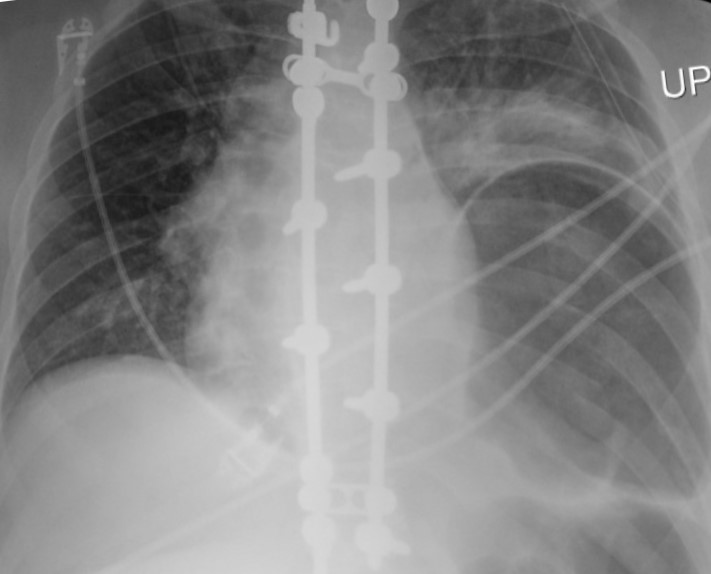

The patient subsequently underwent laparotomy for surgical repair of the renal injury. The follow-up radiograph (Figure 4) after extubation showed a recurrent lower left hemithorax partially lucent mass, increased in size compared to the initial radiograph.

The main radiographic finding suggesting diaphragmatic injury is the elevation of the “diaphragmatic contour” either with or without visualization of a herniating hollow viscus. This may be difficult to differentiate from preexisting hiatal hernia, basilar atelectasis, diaphragmatic eventration, congenital hernias, and phrenic nerve injury which may have a similar appearance. Furthermore, as with our case, positive pressure ventilation may lead to delayed diagnosis due to temporary reduction of the intraabdominal contents. The reported rate of missed diaphragmatic injury on chest radiographs is variable and ranges from 12 to 66%. CT has higher sensitivity and specificity for the diagnosis of diaphragmatic injuries. CT findings include visualization of the discontinuity of the diaphragm (73% sensitivity, 90% specificity), intrathoracic herniation of viscera (55% sensitivity,100% specificity), the collar sign (63% sensitivity, 100% specificity), which refers to a waist like constriction of the herniated viscera where it extends through the diaphragmatic defect, and the dependent viscera sign (90% sensitivity, 100% specificity) which describes the positioning of the abdominal viscera directly anterior to the posterior ribs due to loss of the diaphragmatic structural support.

The prognosis is favorable if diagnosed early and repaired. Missed injuries can lead to delayed herniation of abdominal viscera with resulting morbidity and mortality due to the risk of strangulation.

- Radiographic diagnosis of blunt left diaphragmatic injury may be suggested by elevation of the “diaphragmatic contour,” which can be misinterpreted as the result of other abnormalities.

- In the setting of acute trauma, CT finding of intrathoracic herniation of abdominal contents has very high specificity for diaphragmatic injury and should be managed as such until proven otherwise.